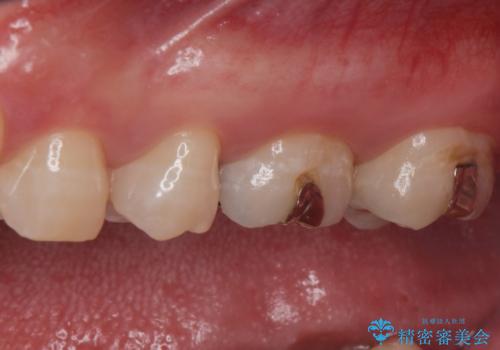

- 詰め物が欠けたとの事で来院。

口腔内を確認したところ詰め物が欠けていたのではなく歯質がう蝕により欠けていました。

拡大鏡下でう蝕を全て取り除き、フルジルコニアクラウンで治療を行いました。

銀の詰め物(保険)は歯質との隙間に細菌や汚れが入りやすく、う蝕の再発のリスクが高いです。